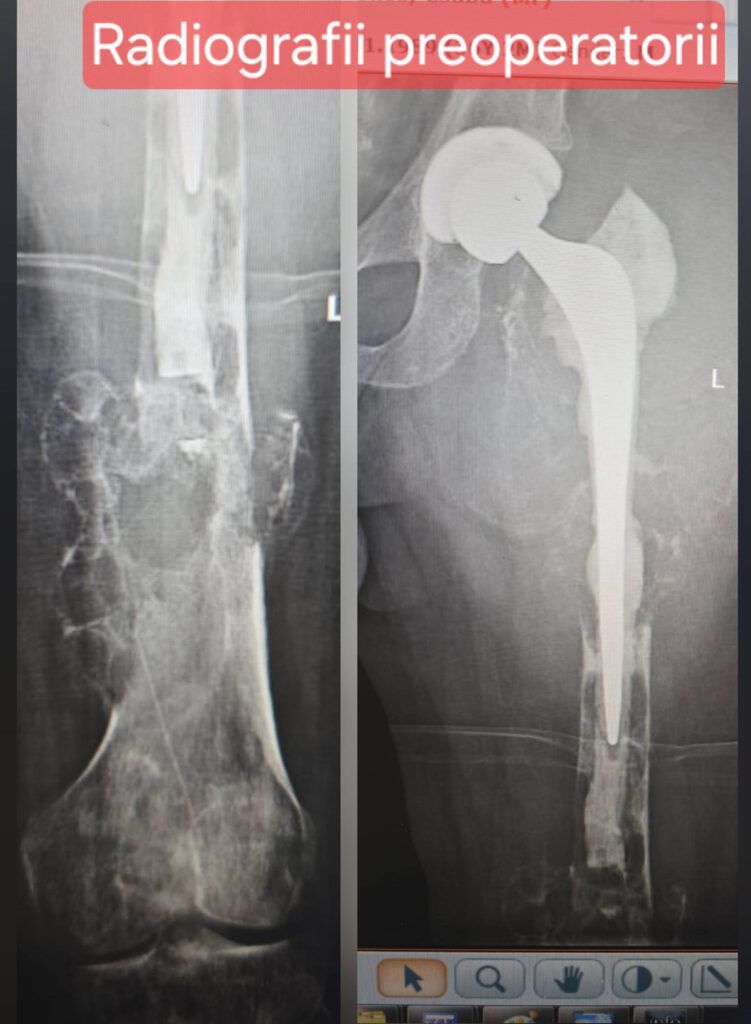

Cazul a implicat un pacient tânăr, de 36 de ani, diagnosticat cu displazie fibroasă femurală și cu antecedente de fractură pe os patologic și artroplastie totală de șold. După mai multe intervenții și complicații, pacientul a fost transferat la SUUB pentru tratament specializat.

Procedura a constat în rezecția completă a femurului și înlocuirea acestuia cu o megaproteză tumorală personalizată, oferind pacientului șansa păstrării membrului și a unei recuperări funcționale semnificative.

- Îndepărtarea integrală a femurului afectat

- Reconstrucția membrului inferior prin implantarea unei megaproteze tumorale personalizate